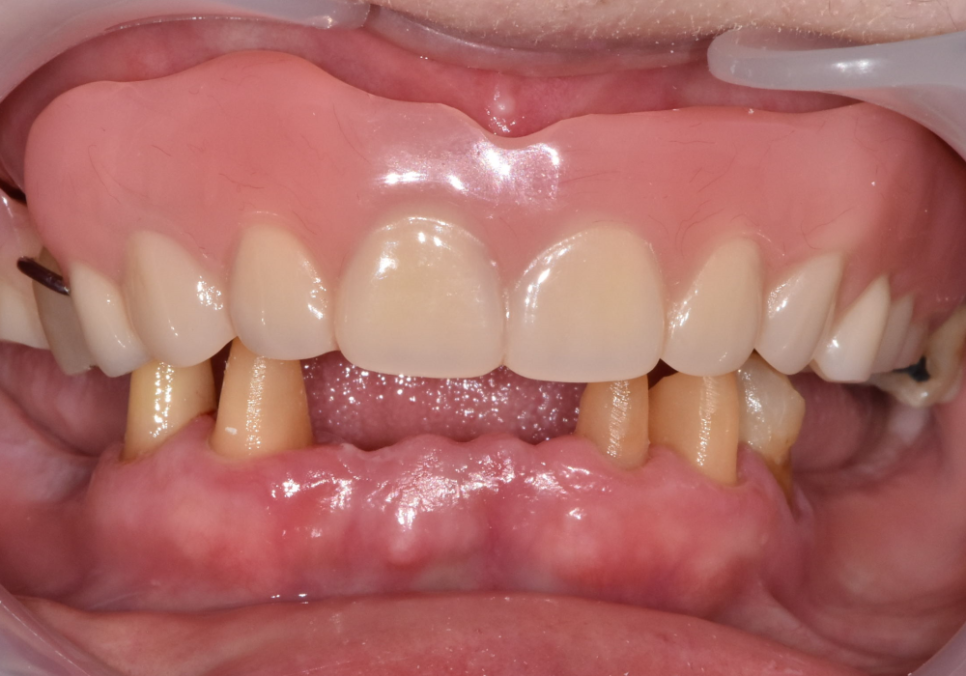

230817(전) 240403 (후)

다행히 뼈이식 부위도 잘 자리를 잡았고

임플란트도 아주 튼튼하게 고정된 것을 확인 후

보철을 올려드렸습니다.

이제는 뿌리만 남았던 치아들 대신

튼튼한 치아로 편안하게

식사하실 수 있게 되었습니다.^^